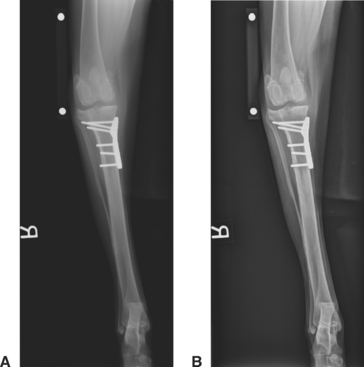

Figure 22-12 Clinical utility of recognition of the Uberschwinger artifact. A, The caudocranial radiographic image of this healed tibial plateau leveling osteotomy procedure shows apparent bone lysis surrounding the tips of the bone screws and underneath the distal portion of the bone plate. B, Following proper image processing, the artifactual “lysis” is gone, indicating that the orthopedic implants are not loosening.